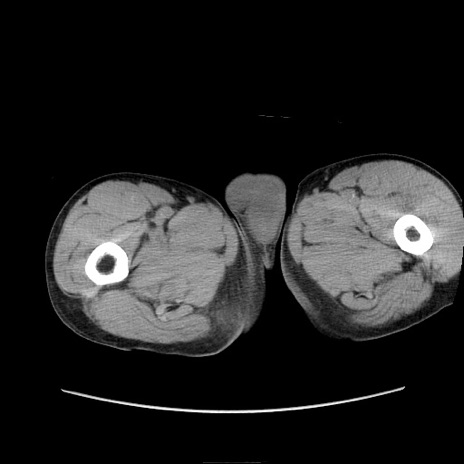

症例11(横断像)

【症例】 60歳代男性

【主訴】 下腹部痛

【現病歴】 本日夜中より下腹部痛の症状認め、受診。

【既往歴】 膀胱癌(膀胱全摘+尿管皮膚瘻術) 、胃癌術後

【身体所見】 BT 35.3℃、PR 58/min、BP 136/98mHg、腹部平坦、軟、腸蠕動音±、ストマ留置あり、左上腹部~正中部に圧痛あり、反跳痛なし。

【データ】WBC 5100、CRP0.01